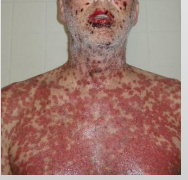

What are characteristics of Stevens-Johnson Syndrome?

Almost Always triggered by drugs (medication)

<10% of body surface is affected

Younger

Initially on trunk

Sever sloughing of skin

What are characteristics of Toxic Epidermal Necrolysis (Lyell disease)?

Almost Always triggered by drugs (medication)

≥30% body surface is affected

Older females

Initially on trunk

Sever sloughing of skin